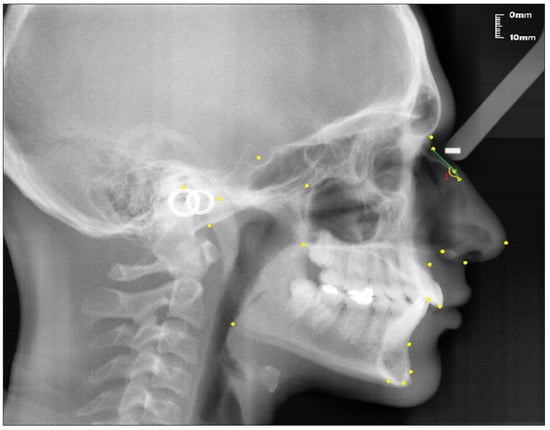

The points used in lateral cephalometric films to evaluate the nasal structure are as follows [1,30]. (see Figure 1)

Figure 1.

Points used in the study.

- Sella (S); the center of Sella turcica.

- Nasion (N); the most anterior point of the sutura frontonasalis and the deepest place of the recess in that region.

- Rhinion (R); the most anterior and inferior point on the tip of the nasal bone.

- Subspinal–point A; below the ANS point, the maxilla is the deepest point of the alveolar bone recess.

- Supramental–point B; deepest midline point on the mandible between infradentale and pogonion.

- Anterior nasal spine (ANS) point; the tip of the median, sharp bony process of the maxilla at the lower margin of the anterior nasal opening.

- N1 point; the most concave point of the nasal bone.

- N2 point; the most convex point of the nasal bone.